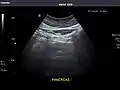

Pancreas